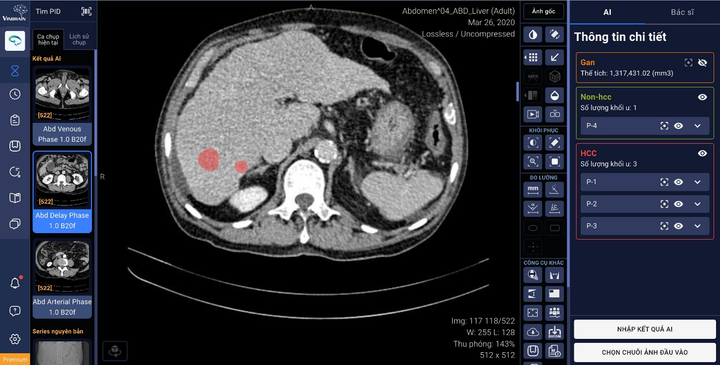

Tính năng mới của phần mềm DrAid™ sẽ hỗ trợ tính năng tự động khoanh vùng và phân loại tổn thương gan bằng ứng dụng trí tuệ nhân tạo, kết nối trực tiếp với PACS (hệ thống lưu trữ và truyền tải hình ảnh y tế) và trả về trên phần mềm kết quả AI khoanh vùng của gan và các tổn thương cũng như phân loại các loại tổn thương.

DrAid™ hỗ trợ tính năng tự động khoanh vùng và phân loại tổn thương gan ứng dụng trí tuệ nhân tạo, kết nối trực tiếp với phần mềm quản lý hình ảnh của bệnh viện (PACS).